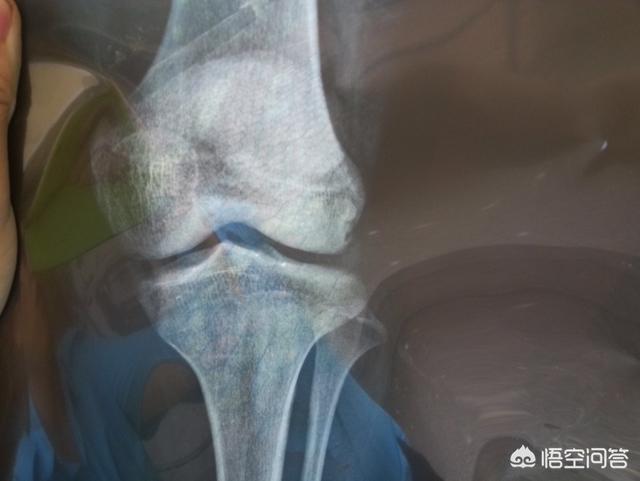

D'un point de vue médical, après les règles, tant que l'épiphyse ne s'est pas refermée, il est encore possible de grandir. Si vous voulez vraiment savoir si vous pouvez encore grandir, le mieux est d'aller à l'hôpital et de passer une échographie pour vérifier votre âge osseux. Tant que votre âge osseux ne dépasse pas votre âge, vous avez la possibilité de grandir.

Par conséquent, si la fille a eu ses règles pendant un an, selon la norme, le développement est déjà tardif, vous pouvez prendre l'enfant pour vérifier l'âge osseux, savoir si l'épiphyse de l'enfant est fermée, si elle a été fermée, alors la moitié de l'année n'a pas grandi, ce qui signifie que l'enfant a cessé de grandir.